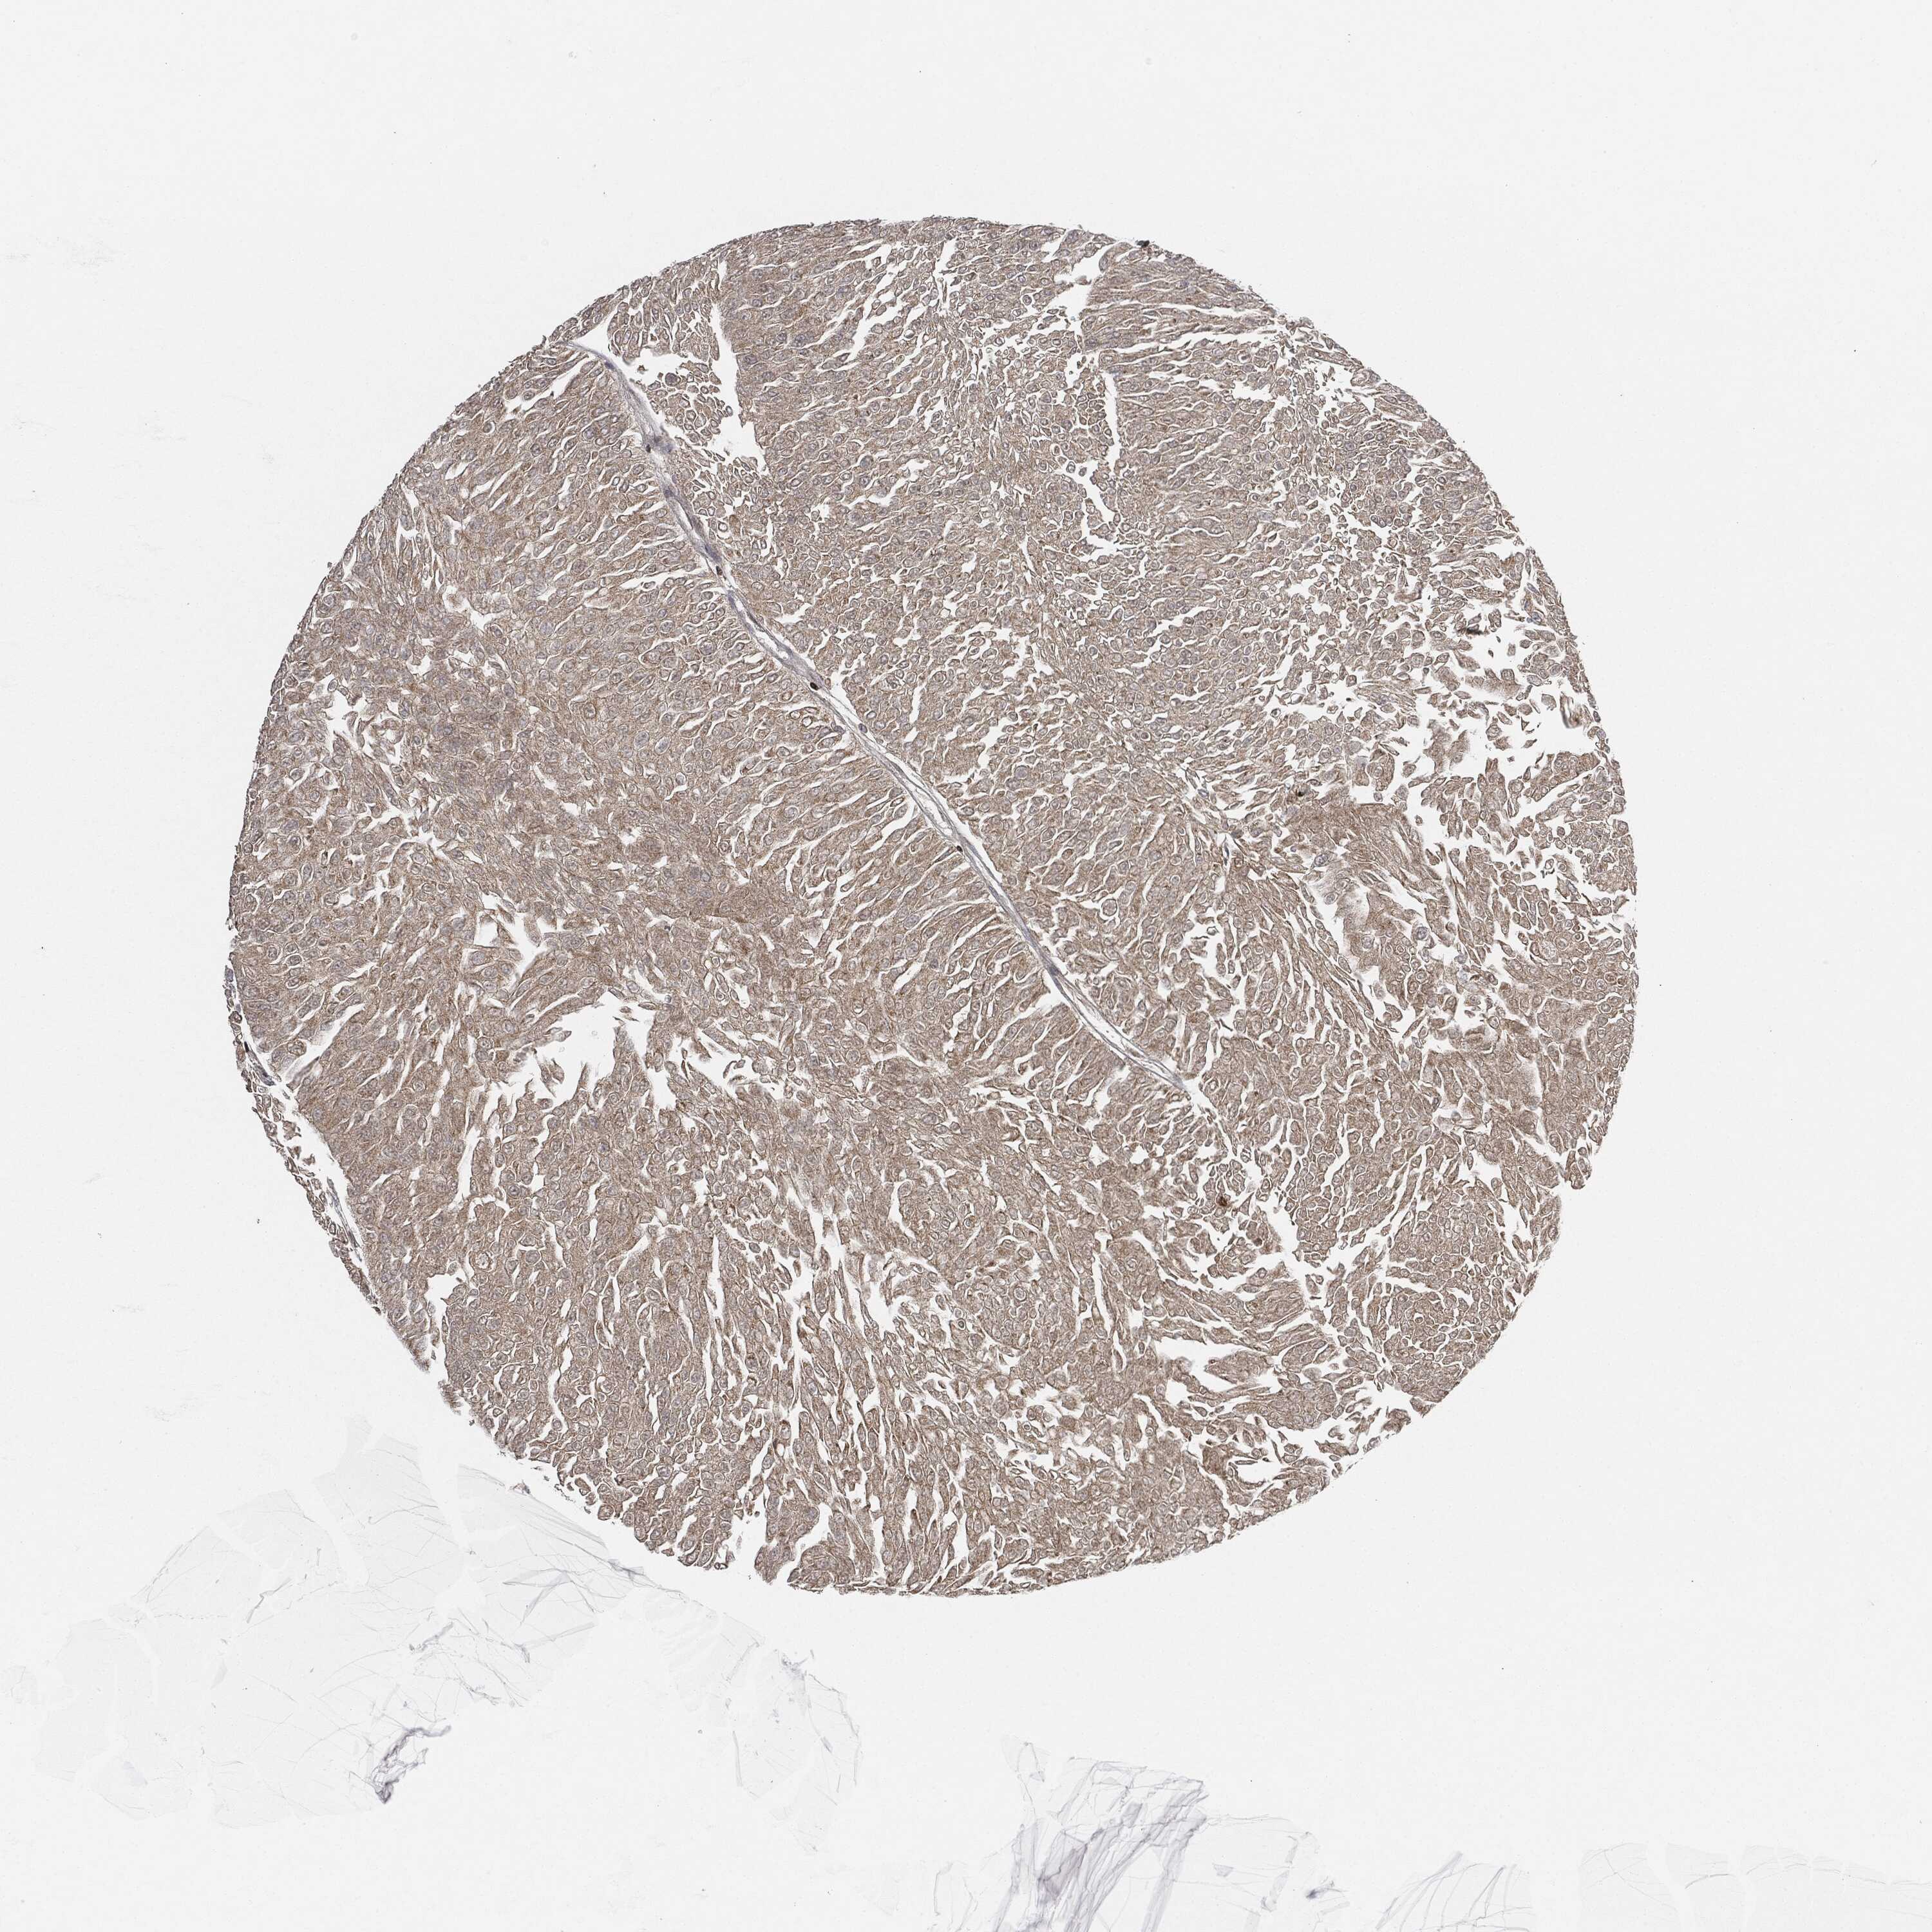

UROTHELIAL CANCER - Protein expressioni

A mouse-over function shows sample information and annotation data. Click on an image to view it in a full screen mode. Samples can be filtered based on level of antibody staining by selecting one or several of the following categories: high, medium, low and not detected. The assay and annotation is described here.

Note that samples used for immunohistochemistry by the Human Protein Atlas do not correspond to samples in the TCGA dataset.

Antibody stainingi

Antibody staining in the annotated cell types in the current human tissue is reported as not detected, low, medium, or high, based on conventional immunohistochemistry profiling in selected tissues. This score is based on the combination of the staining intensity and fraction of stained cells.

Each image is clickable and will lead to virtual microscopy that enables deeper exploration of all samples and also displays staining intensity scores, fraction scores and subcellular localization as well as patient and tissue information for each sample.

CAB080477

Urothelial carcinoma, High grade

Urothelial carcinoma, Low grade

Adenocarcinoma, NOS